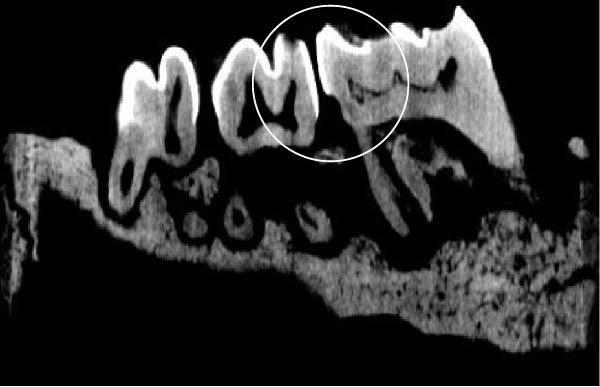

Figure 3 shows the micro‐CT images of OTM in some subgroups.

Figure 3Micro‐CT analysis of OTM after 21 and 40 days: (A) orthodontic treatment/CE injection/stress (chronic); (B) orthodontic treatment/CE injection/stress (acute); (C) orthodontic treatment/stress (chronic); (D) orthodontic treatment/stress (acute); (E) no orthodontic treatment/CE injection/stress (chronic); (F) no orthodontic treatment/CE injection/stress (acute); (G) no orthodontic treatment/no drug (chronic); (H) no orthodontic treatment/no drug (acute).(A)(B)(C)(D)(E)(F)(G)(H)